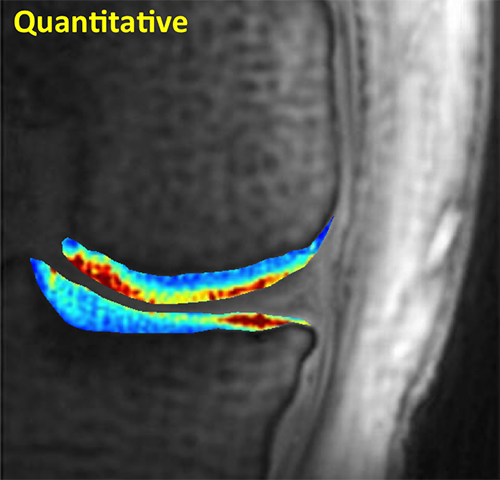

Knee Quantitative

Quantitative MR reveals regional variations in T2 values of articular cartilage with high sensitivity.